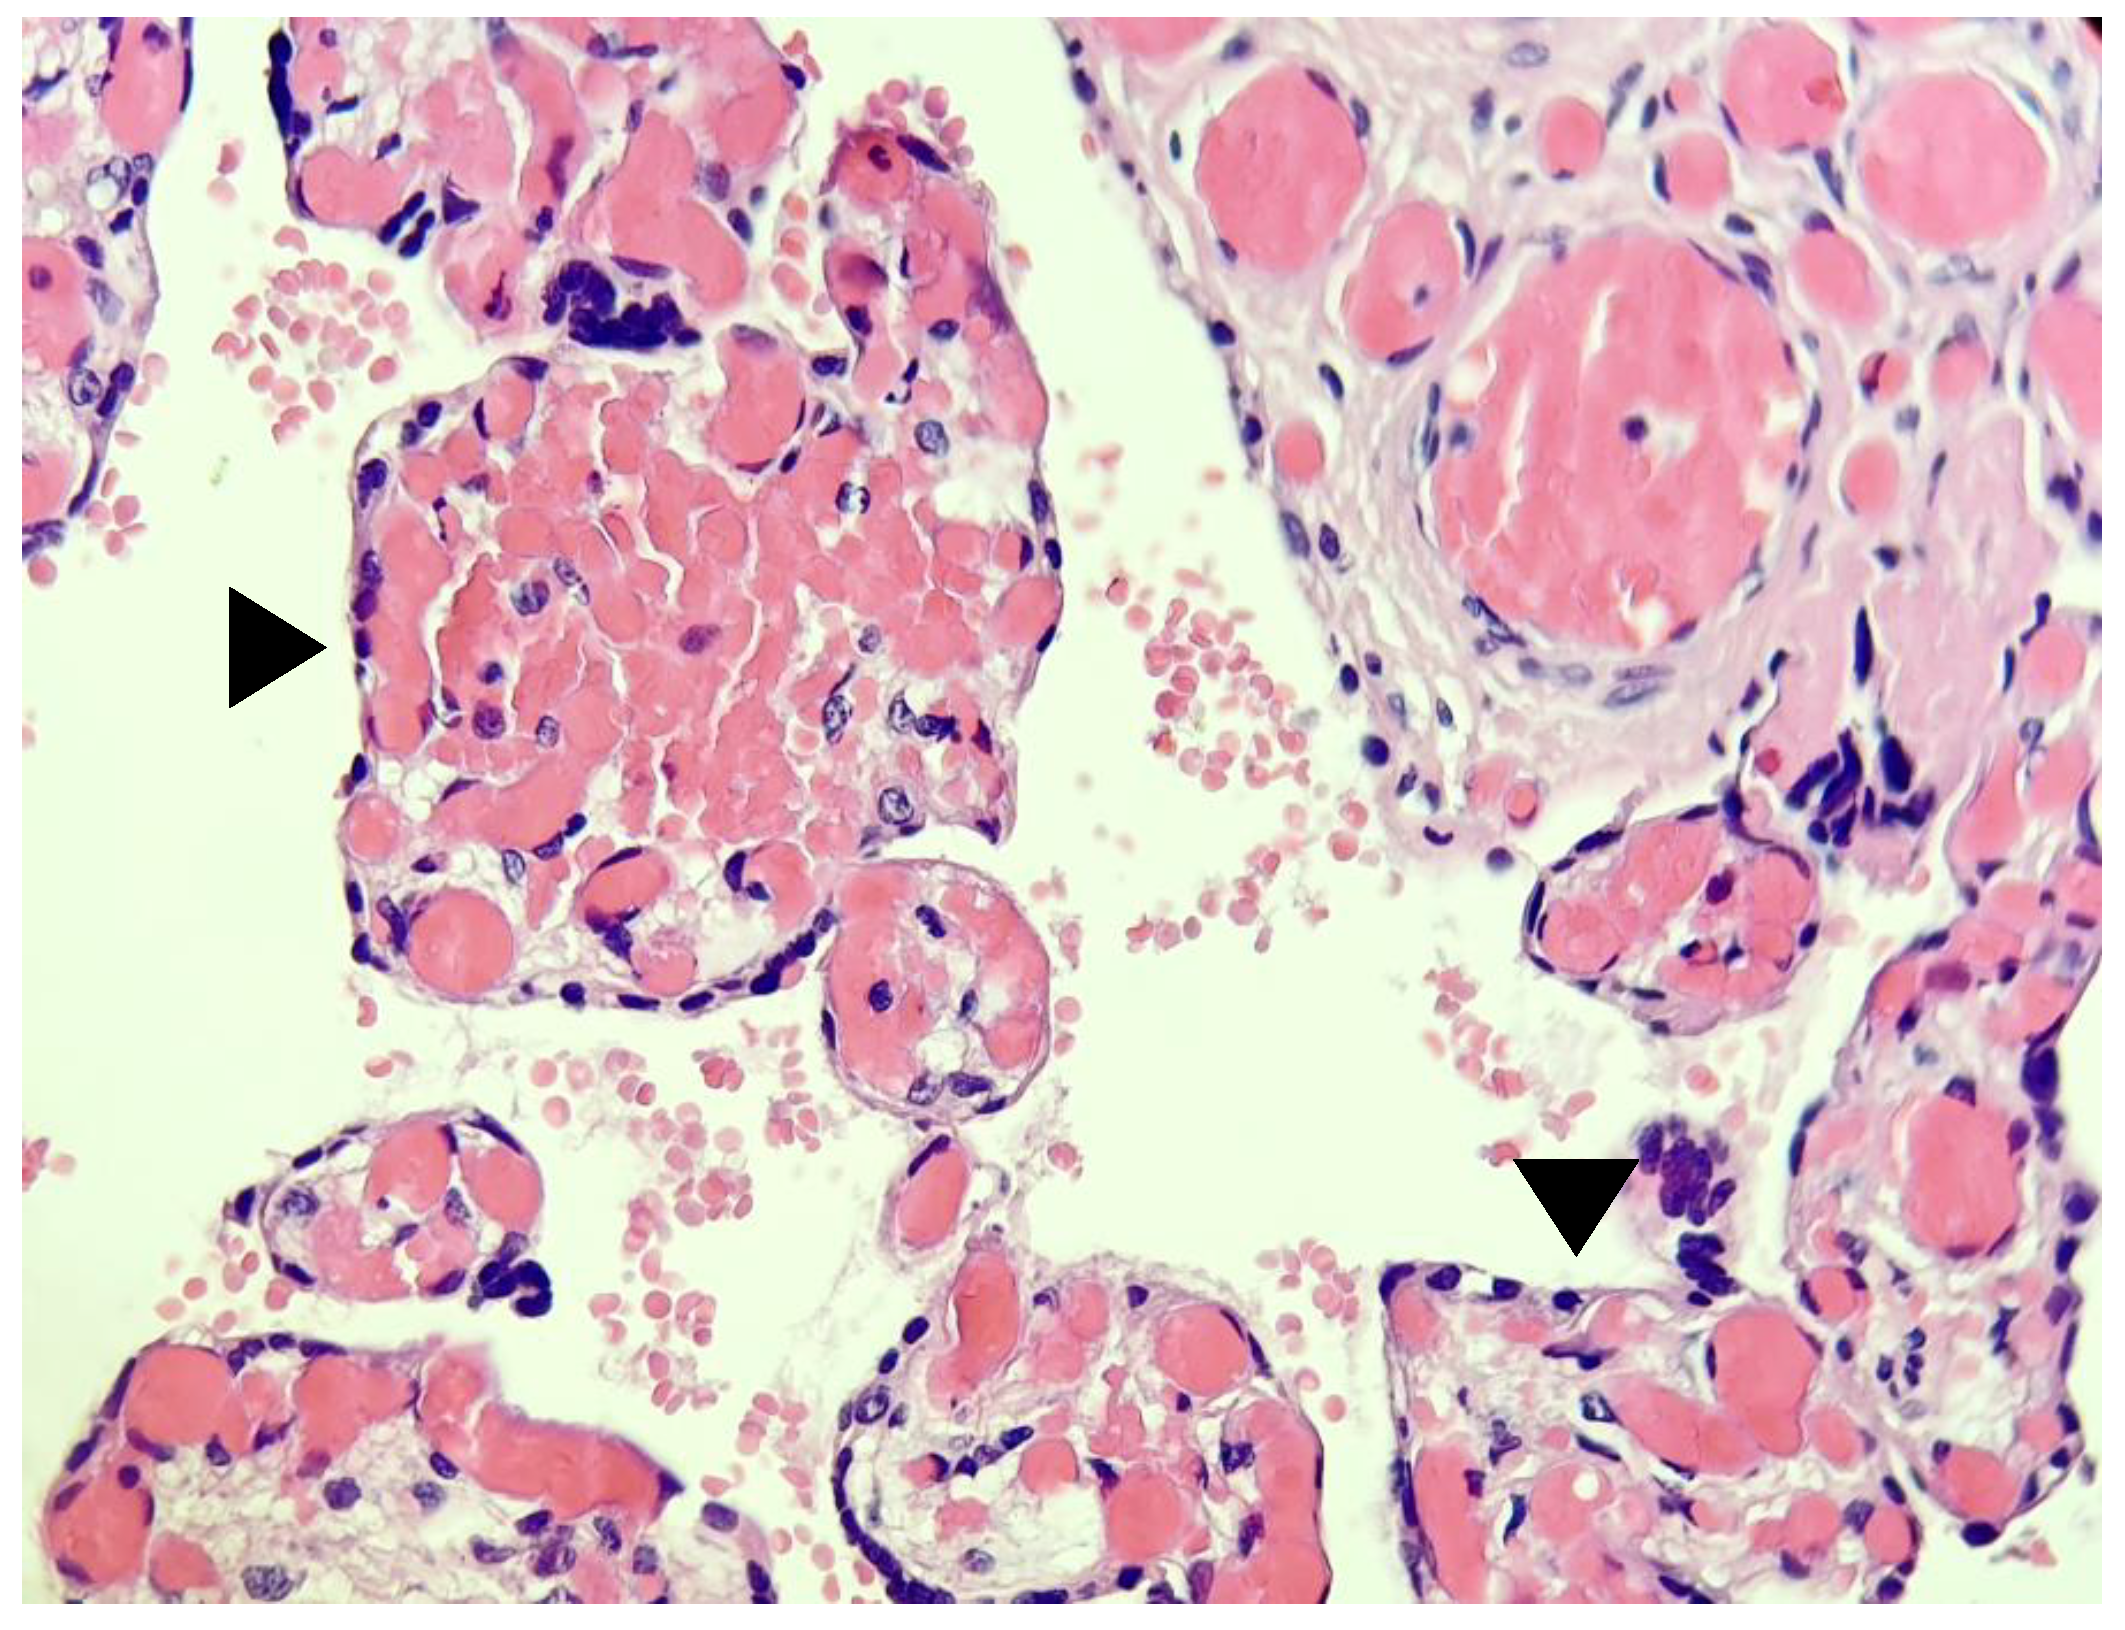

- Shanes, E.D.; Mithal, L.B.; Otero, S.; Azad, H.A.; Miller, E.S.; Goldstein, J.A. Placental Pathology in COVID-19. Am. J. Clin. Pathol. 2020, 154, 23–32. [Google Scholar] [CrossRef] [PubMed]

- Husen, M.F.; van der Meeren, L.E.; Verdijk, R.M.; Fraaij, P.L.A.; van der Eijk, A.A.; Koopmans, M.P.G.; Freeman, L.; Bogers, H.; Trietsch, M.D.; Reiss, I.K.M.; et al. Unique Severe COVID-19 Placental Signature Independent of Severity of Clinical Maternal Symptoms. Viruses 2021, 13, 1670. [Google Scholar] [CrossRef] [PubMed]

- Schoenmakers, S.; Snijder, P.; Verdijk, R.M.; Kuiken, T.; Kamphuis, S.S.M.; Koopman, L.P.; Krasemann, T.B.; Rousian, M.; Broekhuizen, M.; Steegers, E.A.P.; et al. Severe Acute Respiratory Syndrome Coronavirus 2 Placental Infection and Inflammation Leading to Fetal Distress and Neonatal Multi-Organ Failure in an Asymptomatic Woman. J. Pediatr. Infect. Dis. Soc. 2020, 10, 556–561. [Google Scholar] [CrossRef] [PubMed]